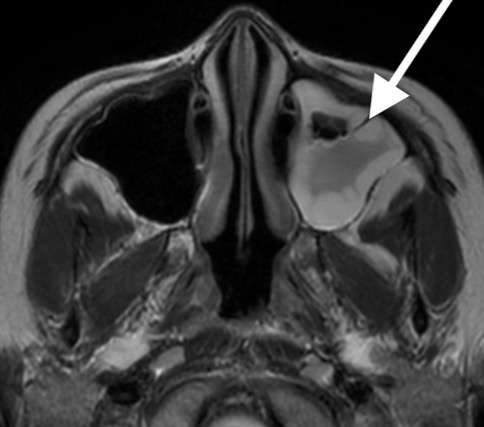

蝶形骨洞炎

元々片頭痛のある40歳女性、突然後頭部の激痛が出現し受診。頭部MRI検査で蝶形骨洞炎を認めました。

しかし、この所見だけでは症状の説明が付かず、頭部MRA検査(脳動脈の撮像)を加えました。

副鼻腔炎による可逆性脳血管攣縮症候群

後大脳動脈(後頭部から上へ行く血管)に多くの狭窄を認め、可逆性脳血管攣縮症候群と診断しました。この症例では、副鼻腔炎が誘因となり可逆性脳血管攣縮症候群を発症した可能性が考えられました。